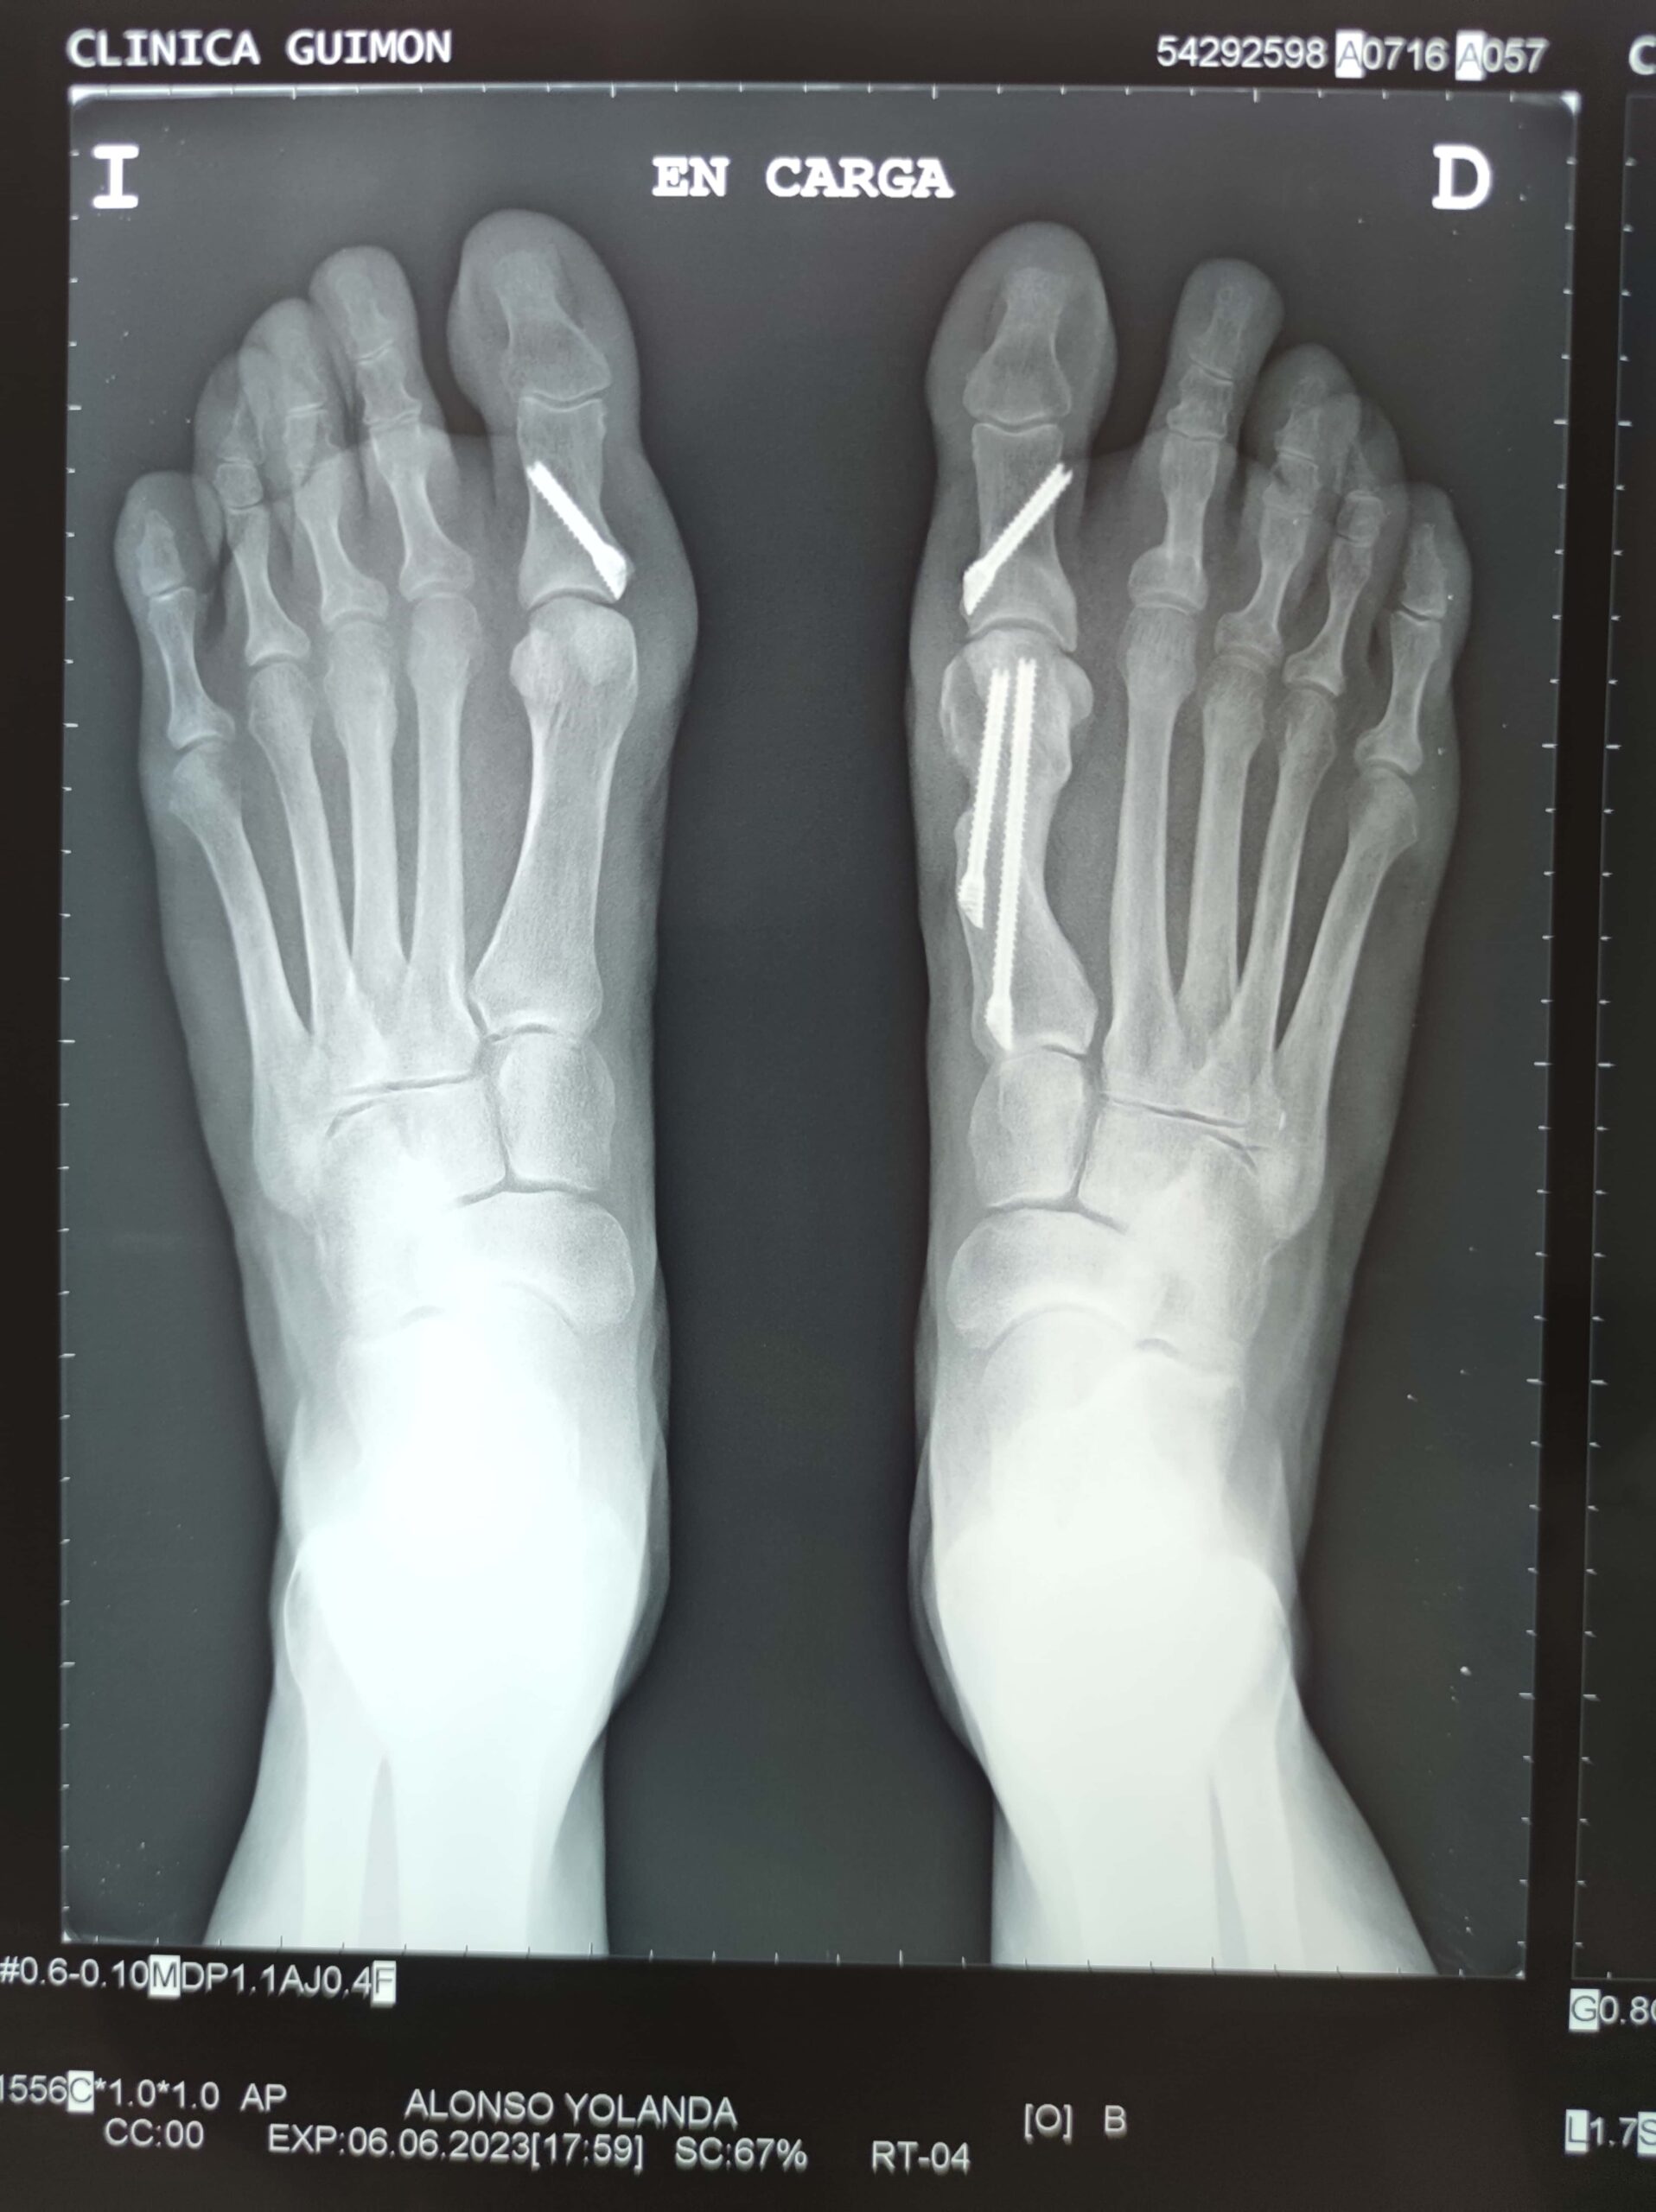

En la mayor parte los pacientes el problema es en los dos pies, aunque varía mucho la magnitud en cada lado.

La cirugía se basa en cortes sobre los huesos para obtener una alineación adecuada del dedo gordo, utilizando tornillos u otro tipo de material para mantener la reconstrucción realizada.

Habitualmente se realiza cirugía a través de incisiones muy pequeñas denominada percutánea (cirugía mínimamente invasiva), a veces es mal llamada láser. A veces tenemos que recurrir a la cirugía abierta normal también. La técnica dependerá de cada caso en concreto, ya que toda cirugía tiene su indicación.